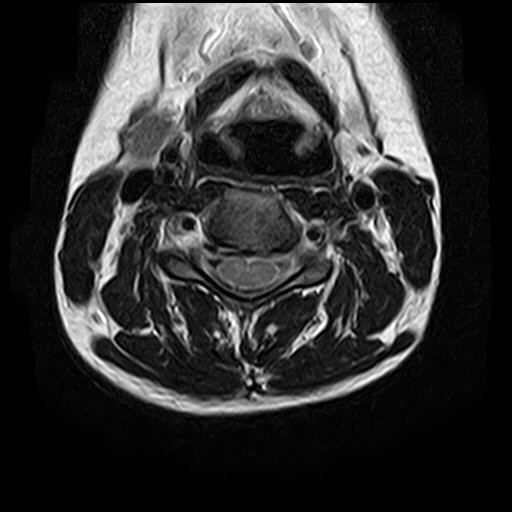

• 1번 째 사진

• 2번 째 사진

• 3번 째 사진

• 4번 째 사진

• 5번 째 사진